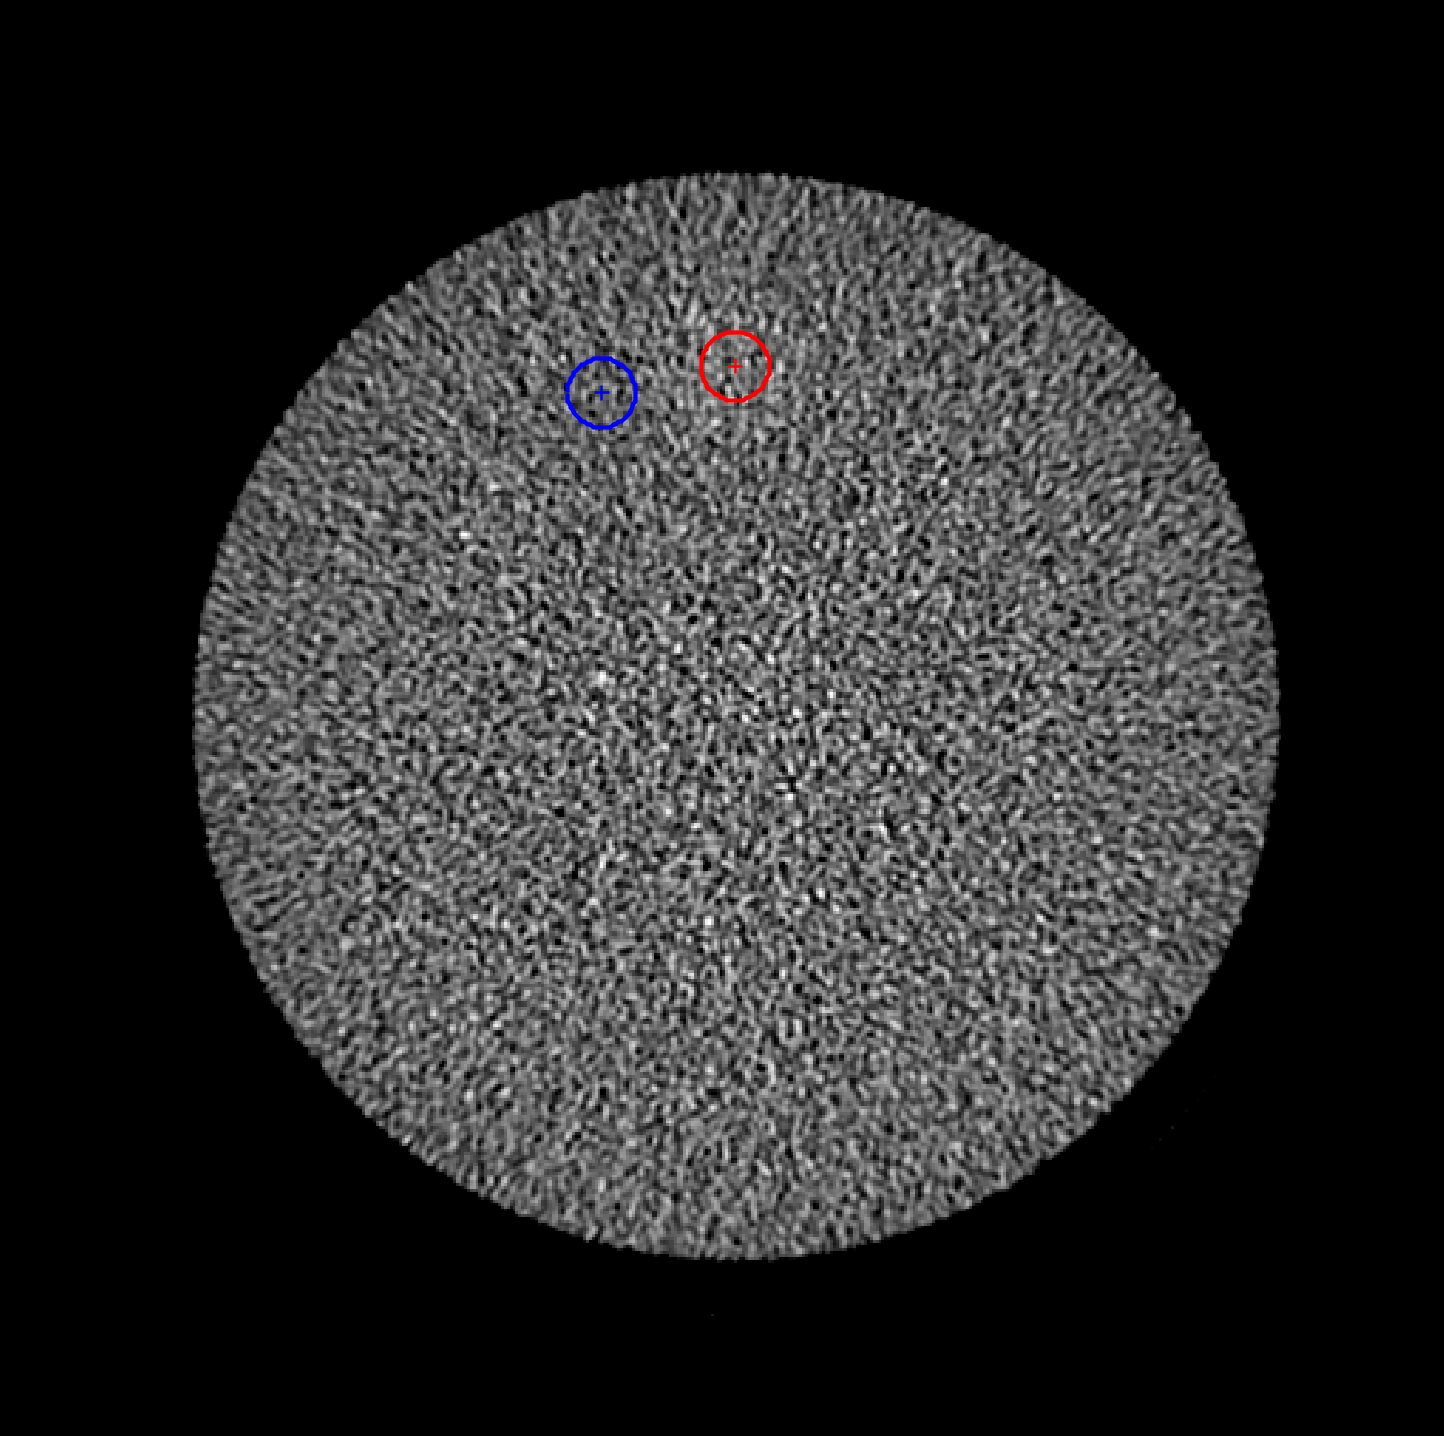

Low Contrast Resolution

The low contrast module contains a single 25 mm diameter cylinder at the top and four cylinders each of 6, 5, 4, 3, 2 mm diameters in that order arranged counter clockwise.¹

The image window width is set to 100 and window level is set to 100.

Contrast to noise is calculated as

| A - B | ÷ SD

Where

- A is the mean pixel value of an ROI in the center of the 25 mm cylinder with an approximate radius of 5.64 mm (100 mm²). It is marked in red on the figure above. The plus sign is the center of the ROI.

- B is the mean pixel value of an ROI centered between the 25 mm cylinder and the four 6 mm cylinders with an approximate radius of 5.64 mm (100 mm²). This area contains no cylinders and is used for the background measurement. It is marked in blue on the figure above. The plus sign is the center of the ROI.

- SD is the standard deviation of pixel values for B